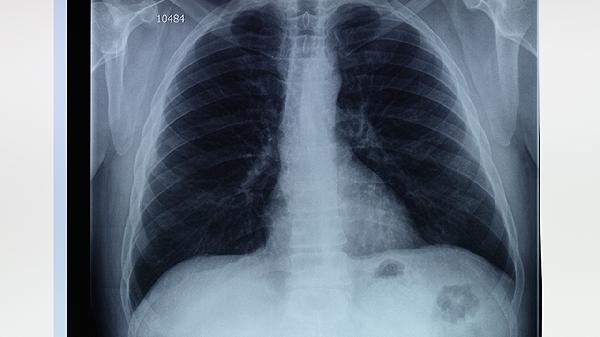

1、影像学检查是诊断肺大泡的首要方法。胸部X线可以初步发现肺大泡的存在,表现为肺部透亮区域,但分辨率有限。CT扫描尤其是高分辨率CT,能够更清晰地显示肺大泡的大小、位置和数量,帮助鉴别肺大泡与其他肺部疾病如肺气肿、肺囊肿等。